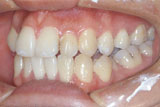

그림 2. 안면비대칭을 주소로 내원한 23세 남자환자로서 골격성 3급 부정교합과 함께 좌측의 반대교합을 보여주고 있다. menton이 심하게 좌측으로 편위되어 있어 우측과두가 좌측에 비해 과성장한 것에 의해 나타난 RM type의 안면비대칭으로 보여졌다.

그림 3. 정모두부방사선사진의 투사도를 작성하고 분석을 시행한 결과 Me은 편위된 반면 ramus length의 좌우차이는 보이지 않아 기계적으로는 M type으로 판정되었다. 그렇다면 본 환자의 이부편위는 어떻게 나타났는가?어느 부위의 좌우차이가 본 환자의 이부편위에 기여하였는지 2차원적인 방사선사진만으로 잘 파악이 되지 않는다.